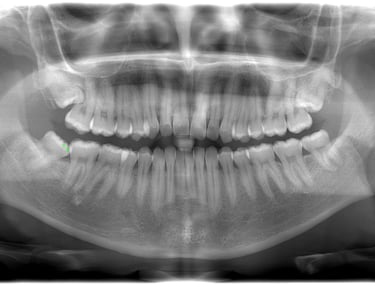

RX DIGITAL EXTRAORAL Ofrecemos una amplia gama de servicios en el área de las radiografías, está línea tenemos una serie de sublineas que se adaptan a las necesidades de cada tratamiento y requerimiento.

- Panorámica: Es una toma de la boca entera incluyendo dientes mandíbulas Inferior y Superior, estructuras y tejidos